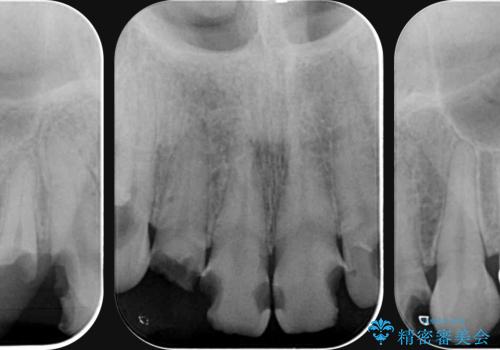

- 放置した虫歯の歯がボロボロになってしまい治療を希望され来院されました。

残根状態の歯、神経まで虫歯が達し失活した歯、歯肉縁下まで及んだ虫歯が多数認められます。

まず虫歯を拡大鏡、マイクロスコープ下で丁寧に取り除き歯肉縁下の虫歯を歯周外科により解決したのち、ジルコニアクラウン製作を行っていきます。